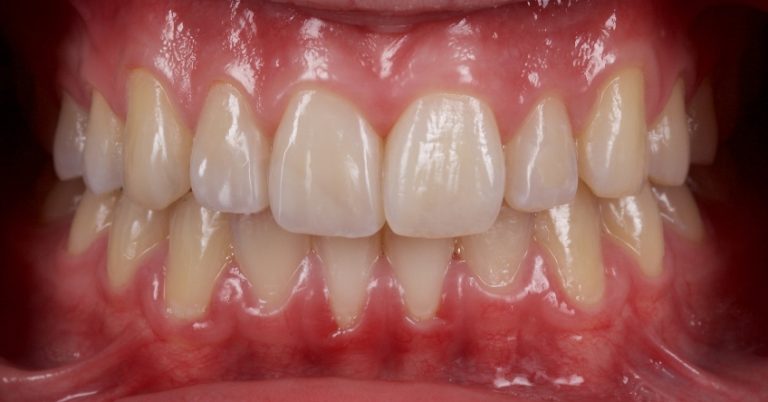

Using this tooth shade matching technique makes selecting a reference tooth shade easy, efficient, and predictable for restorative dentists chairside.

One key aspect of esthetic dentistry is using geometric proportions, like the golden percentage, to create predictable and pleasing restorative outcomes.